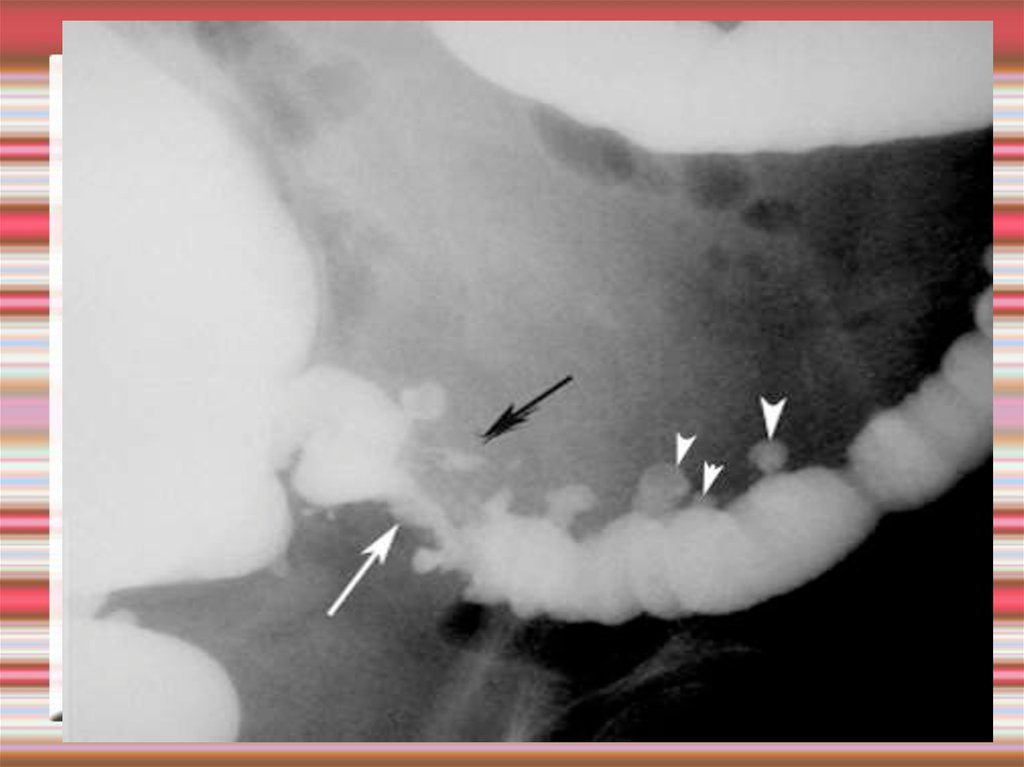

7. Диагностика дивертикулеза толстой кишки

Ирригография

дивертикулез толстой кишки

8. Ирригография дивертикулез толстой кишки